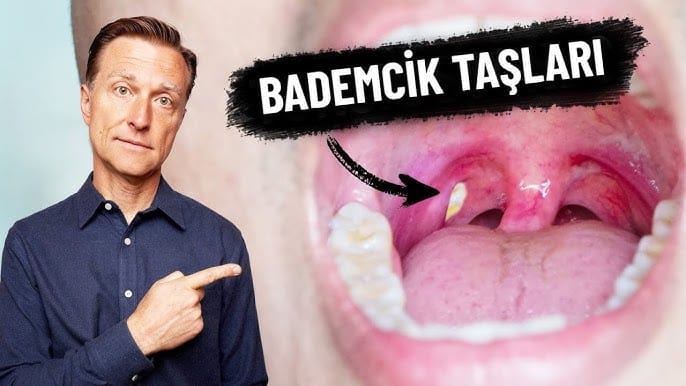

Bademcik taşları nedir?

Bademcik taşları, bademciklerin yüzeyinde küçük çakıl taşları belirdiğinde ortaya çıkar. Taşlar beyaz veya sarı görünebilir. Bademcik dokusunun derinliklerinde oluşurlarsa, taşlar görünmeyebilir.

Bademcik kızarıklığı ve tahrişi, bademcik taşlarının yaygın belirtileridir. Bazı durumlarda, bademcik taşları kronik bademcik iltihabına veya bademcik iltihabı adı verilen bademcik enfeksiyonuna neden olabilir.